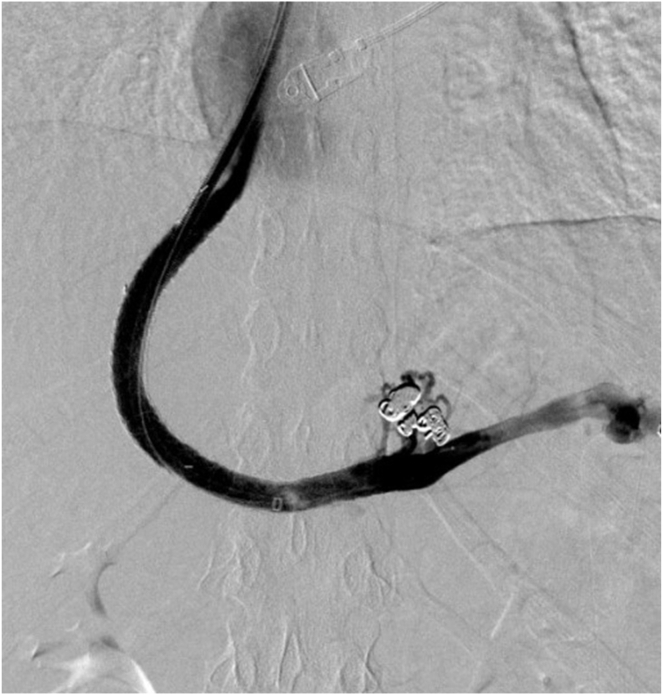

门静脉再通经颈静脉肝内门静脉系统分流术(pvrtips)是一种安全有效的门静脉高压症(PH)减压手术。在这个简短的病例系列中,2名患有慢性非肝硬化门静脉血栓的女性接受了PVR-TIPS治疗。两个病人都希望怀孕。如果不治疗她们的PH值,她们的怀孕会造成危及生命的静脉曲张出血的重大风险。两名患者对手术耐受良好,分娩时没有出现PH并发症。在未来希望怀孕的非肝硬化门静脉血栓患者中,PVR-TIPS应被考虑作为PH的最终治疗。

Portal vein recanalization transjugular intrahepatic portosystemic shunt (PVR-TIPS) is a safe and effective procedure for decompression of portal hypertension (PH). In this short case series, 2 women with chronic noncirrhotic portal vein thrombosis were treated with PVR-TIPS. Both patients hoped to conceive. Without treatment for their PH, their pregnancies posed a significant risk of life-threatening variceal bleeding. Both patients tolerated the procedure well and delivered without complications of PH. In future cases of noncirrhotic portal vein thrombosis in patients hoping to conceive, PVR-TIPS should be considered for definitive treatment of PH.